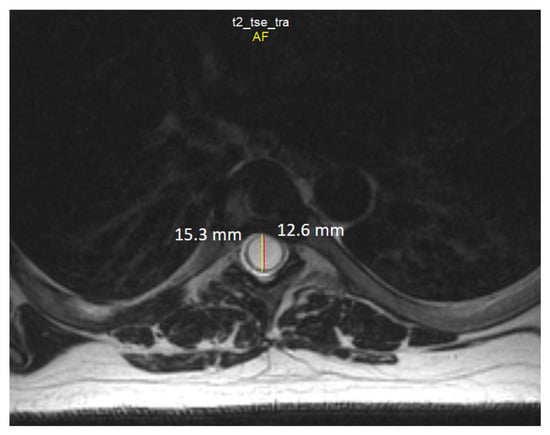

2.4. Neuroimaging